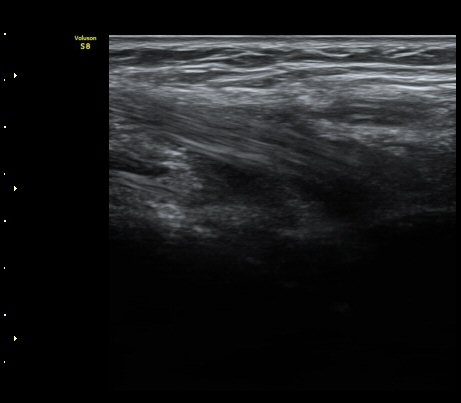

À̵ιڱ٠ÈûÁÙ Á¾´Ü¸é°Ë»ç¿¡¼­ ÈûÁÙÀÌ Àú¿¡ÄÚ°í °üÂûµÇ°í ÈûÁÙ ÁÖº¯ÀÇ ¼ö¾×Àú·ù°¡

¾Ö¸ÅÇÏ°Ô °üÂûµÈ´Ù(±×¸² 7). ŽÃËÀÚ ±ÙÀ§ºÎ¸¦ ÇǺÎÂÊÀ¸·Î ´©¸£´Ï ÈûÁÙÀÌ °í¿¡ÄÚ·Î

°üÂûµÇ°í ¼ö¾×Àú·ùµµ ¶Ñ·ÈÇÏ´Ù(±×¸² 8).